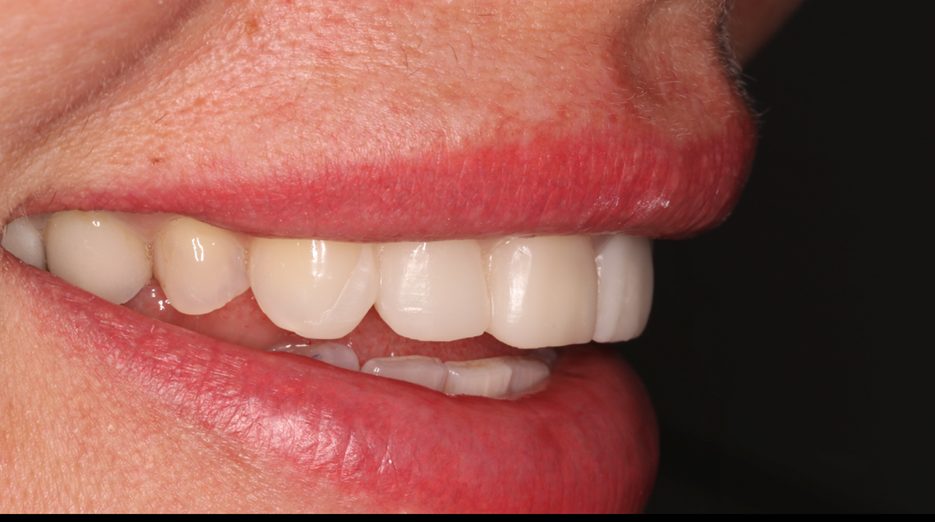

Пациентка И., 43 лет, обратилась в клинику с жалобами на эстетику передних зубов (рис. 1). Зуб 21 ранее проходил эндодонтическое лечение более шести лет назад. На момент первичного осмотра зуб был восстановлен временной композитной коронкой. Зуб 11 имел более тёмный оттенок по сравнению с верхними боковыми резцами. После обсуждения плана лечения пациентка выбрала восстановление зубов с 13 по 23 с использованием керамических реставраций.

Рис. 1. A – вид передней группы зубов с ретракторами. Зуб 21 ранее был пролечен эндодонтически и восстановлен временной коронкой.

B – улыбка пациента.